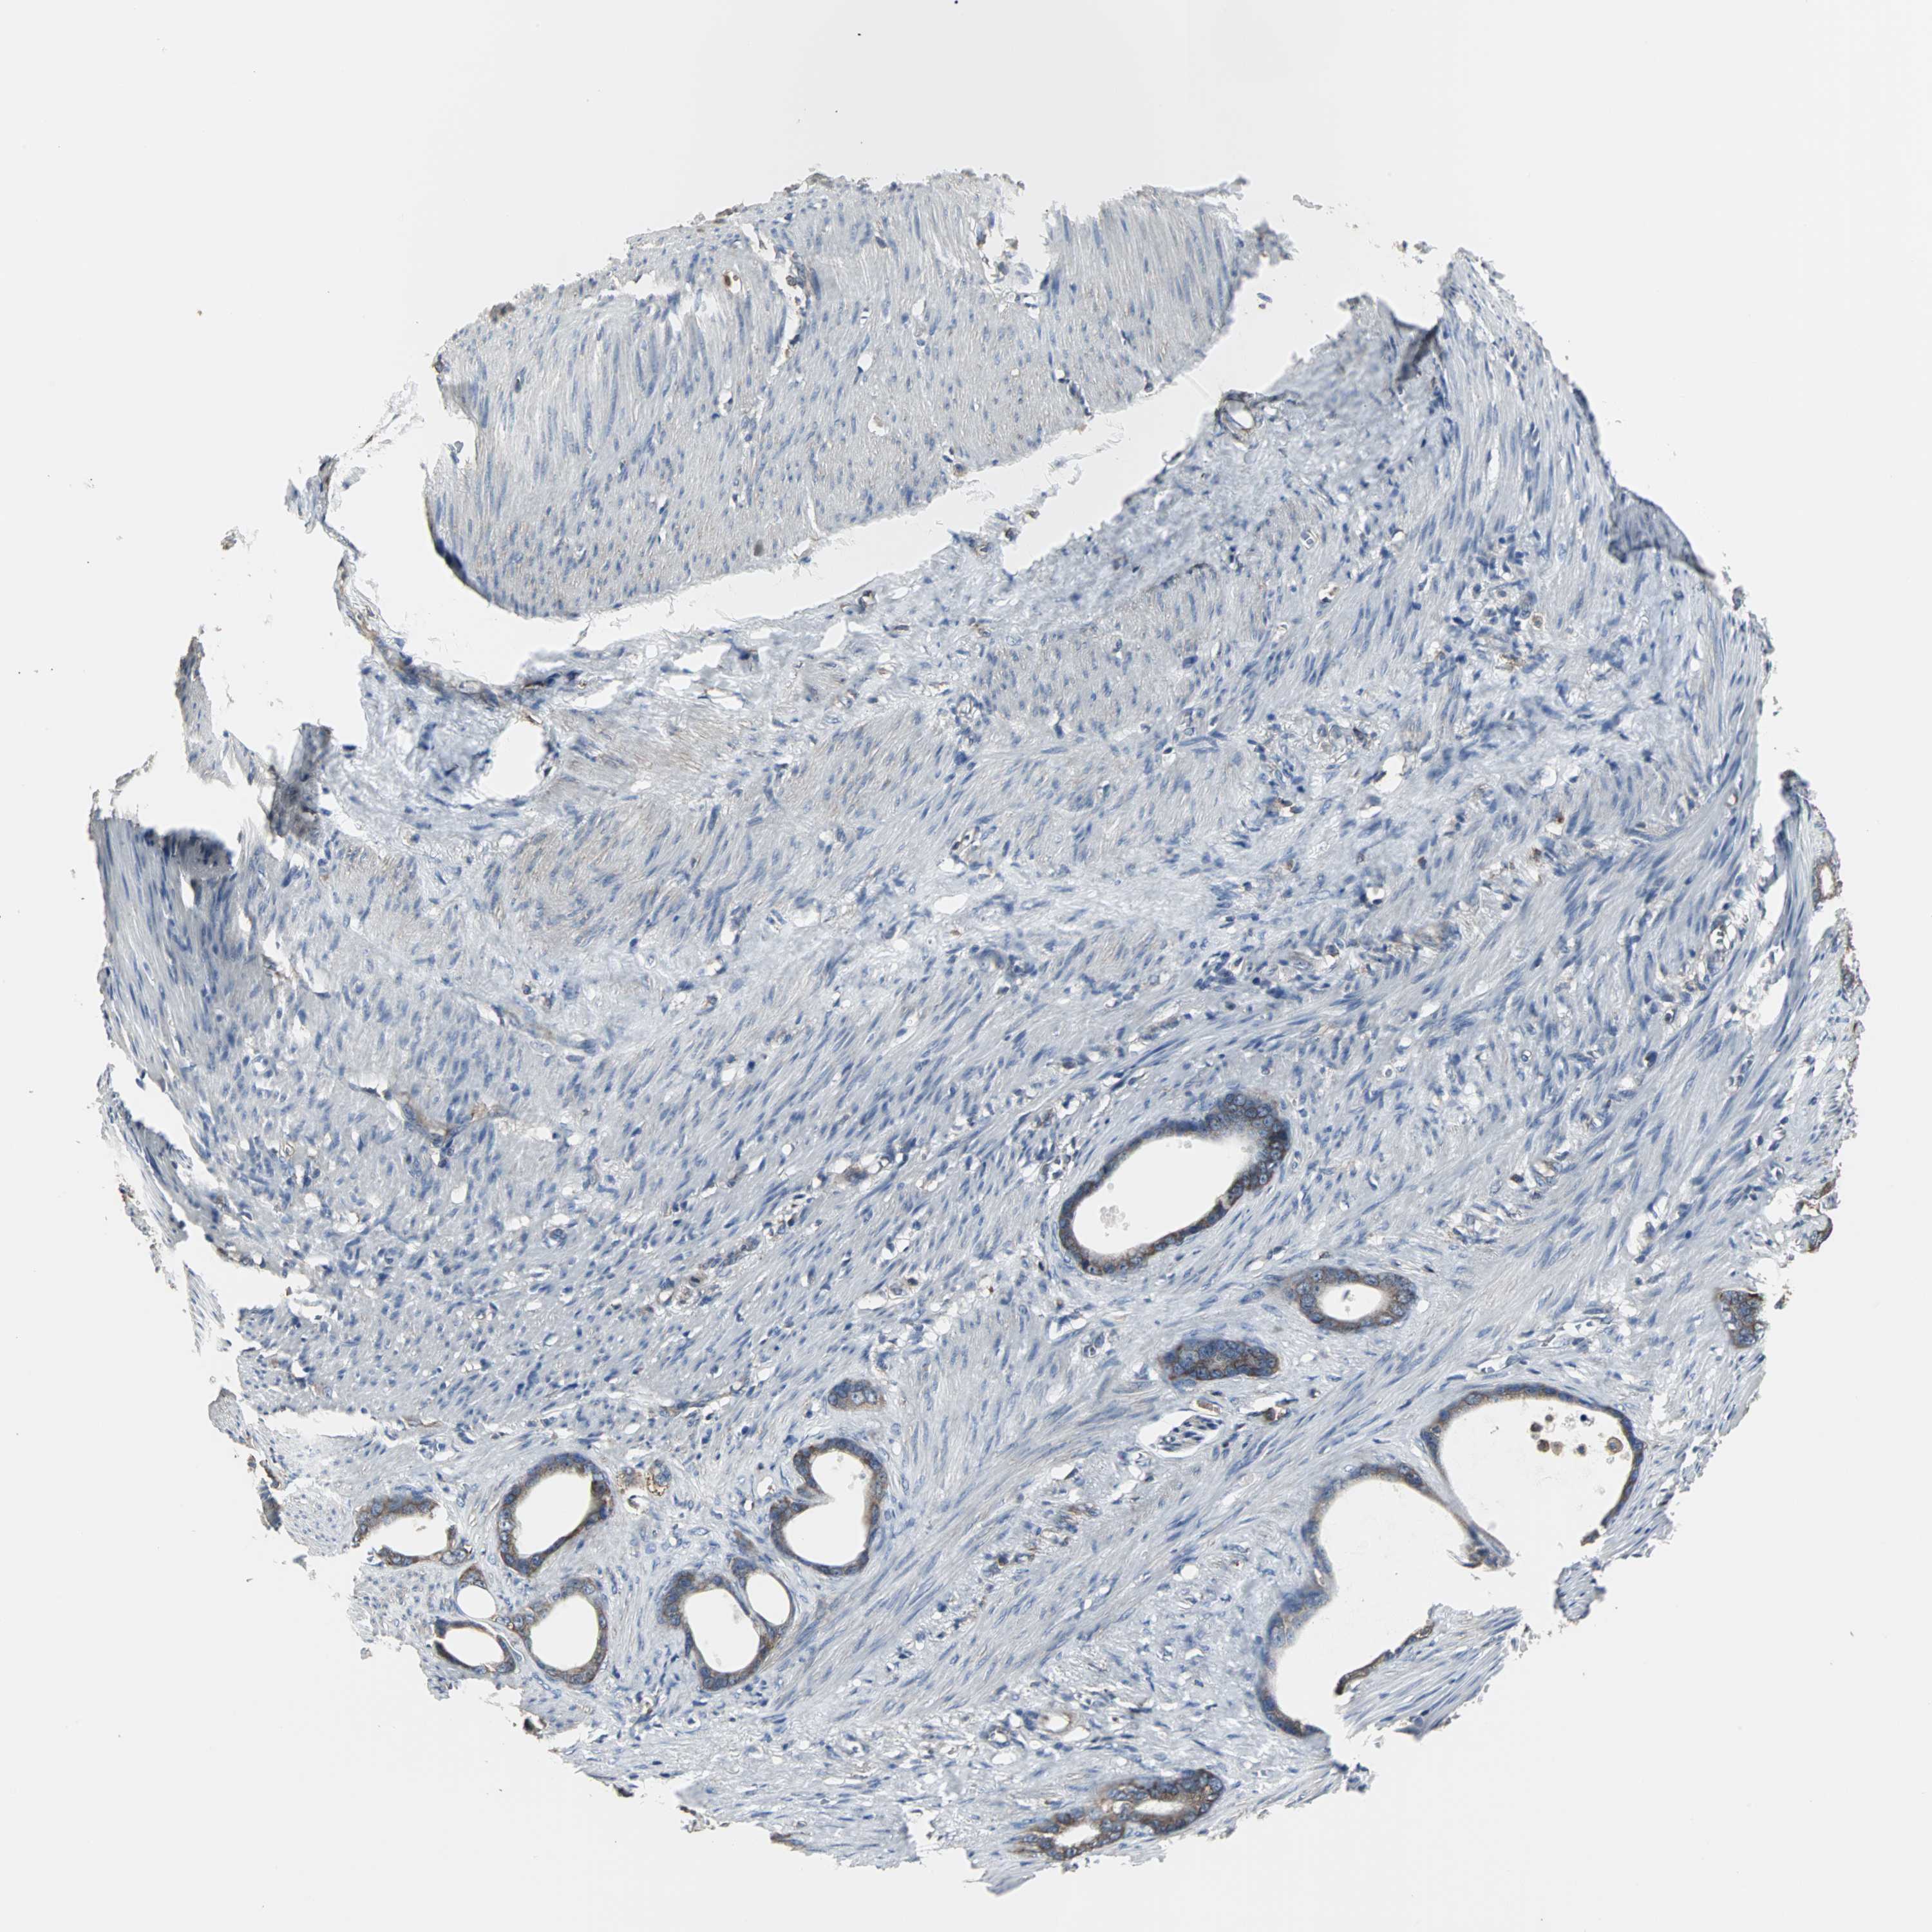

STOMACH CANCER - Protein expressioni

A mouse-over function shows sample information and annotation data. Click on an image to view it in a full screen mode. Samples can be filtered based on level of antibody staining by selecting one or several of the following categories: high, medium, low and not detected. The assay and annotation is described here.

Note that samples used for immunohistochemistry by the Human Protein Atlas do not correspond to samples in the TCGA dataset.

Antibody stainingi

Antibody staining in the annotated cell types in the current human tissue is reported as not detected, low, medium, or high, based on conventional immunohistochemistry profiling in selected tissues. This score is based on the combination of the staining intensity and fraction of stained cells.

Each image is clickable and will lead to virtual microscopy that enables deeper exploration of all samples and also displays staining intensity scores, fraction scores and subcellular localization as well as patient and tissue information for each sample.

Antibody HPA006979

Staining

High

Medium

Low

Not detected

Intensity

Strong

Moderate

Weak

Negative

Quantity

>75%

75%-25%

<25%

None

Location

Nuclear

Cytoplasmic/membranous

Cytoplasmic/membranous,nuclear

Adenocarcinoma, NOS

Adenocarcinoma, High grade